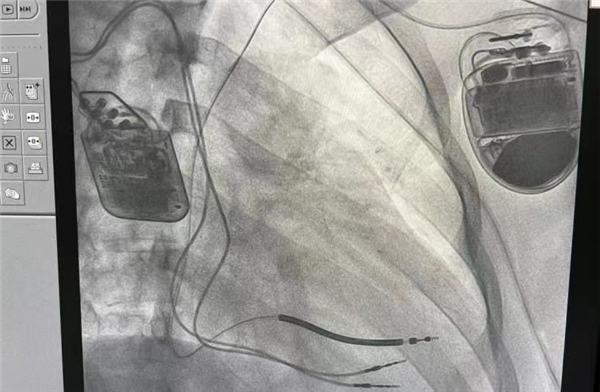

10月30日上午,由北京阜外医院心律失常诊治中心副主任华伟教授亲自主刀,阜外深圳医院王靖教授、廖志勇教授、李华龙教授配合进行的中国首例心脏收缩力调节器(CCM)植入手术在位于深圳南山区中国医学科学院阜外医院深圳医院成功完成,该手术填补了心衰治疗未竟空白,让心衰患者重新见到了生命的曙光。

据悉,这次的手术是一位 17 岁的男性患者,属于扩张性心肌病。华伟教授介绍,“患者去年曾发生过心室颤动,后来植入了埋藏式除颤器,在经过大量的药物治疗以后,心功能仍然不缓解。我们在手术之前,测量的射血分数只有 25%,心脏扩大。今天的手术非常成功,我们术后进行了测试,各项参数都非常理想。”

值得注意的是,此次手术引入的植入式心脏收缩力调节器(OPTIMIZER Smart)是一种先进的心力衰竭治疗装置,今年年内才获得中国的上市批准,首次在深圳运用Optimizer Smart系统的心脏收缩力调节(CCM)疗法,通过微创手术将刺激电极植入到患者心室,在心脏搏动的绝对不应期对心肌释放电刺激,这种电刺激不会改变患者心肌的搏动频率,但是可以通过一系列信号通路改善心肌的生理状态,加强心脏收缩能力,从而改善心衰患者心功能。